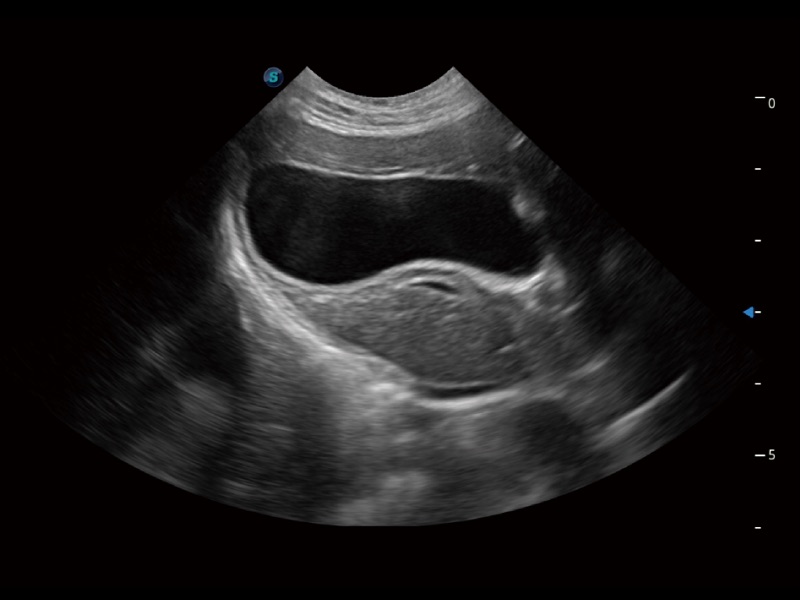

一键自动识别膀胱壁及自动测量膀胱容积,不受膀胱形状和大小的限制,帮助医生快速精准获得测量的数据。

ProPet 70专为动物医生设计,对不同的动物体型和生理结构作出了针对性的优化。通过动物影像专用软件,可满足个性化的应用需求,帮助动物医生获得更精确的诊断数据。

ProPet 70 全新的动物超声智能软件和丰富的探头群,为动物医生提供了高清晰度和精细分辨率的图像,无论在宠物、马科、畜牧还是实验室动物等应用中都可以轻松应对,为您的日常工作带来满意的体验。